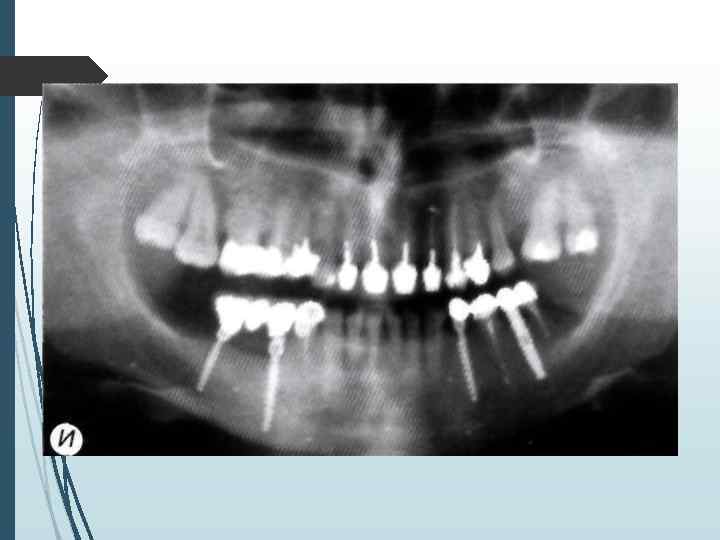

Однако следует учитывать, что даже при правильной укладке и методике ортопантомография даёт искажения реальных размеров челюстей до 10% по вертикали и до 20% по горизонтали. При неправильном положении пациента во время обследования или нарушении режима работы ортопантомографа искажения (увеличение размеров) могут достигать 32% по вертикали и 50 -70% по горизонтали

Компьютерная томография является одним из наиболее информативных методов рентгенологического обследования. С высокой степенью достоверности она позволяет определить высоту и ширину кости, топографию нижнечелюстных каналов и верхнечелюстных пазух, особенности архитектоники различных отделов челюстей, соотношение последних, а также создать трёхмерное изображение лицевого отдела черепа